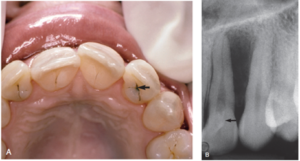

A 9-year boy has pain, is attending today with swelling in the infraorbital region and high fever 39.8’C. Tooth 12 is extremely painful to percussion, no caries detected.

PA Xray was given of 13,12,11 – it shows extremely immature root of tooth #12 with dens invaginatus, retained #53 and unerupted #131)